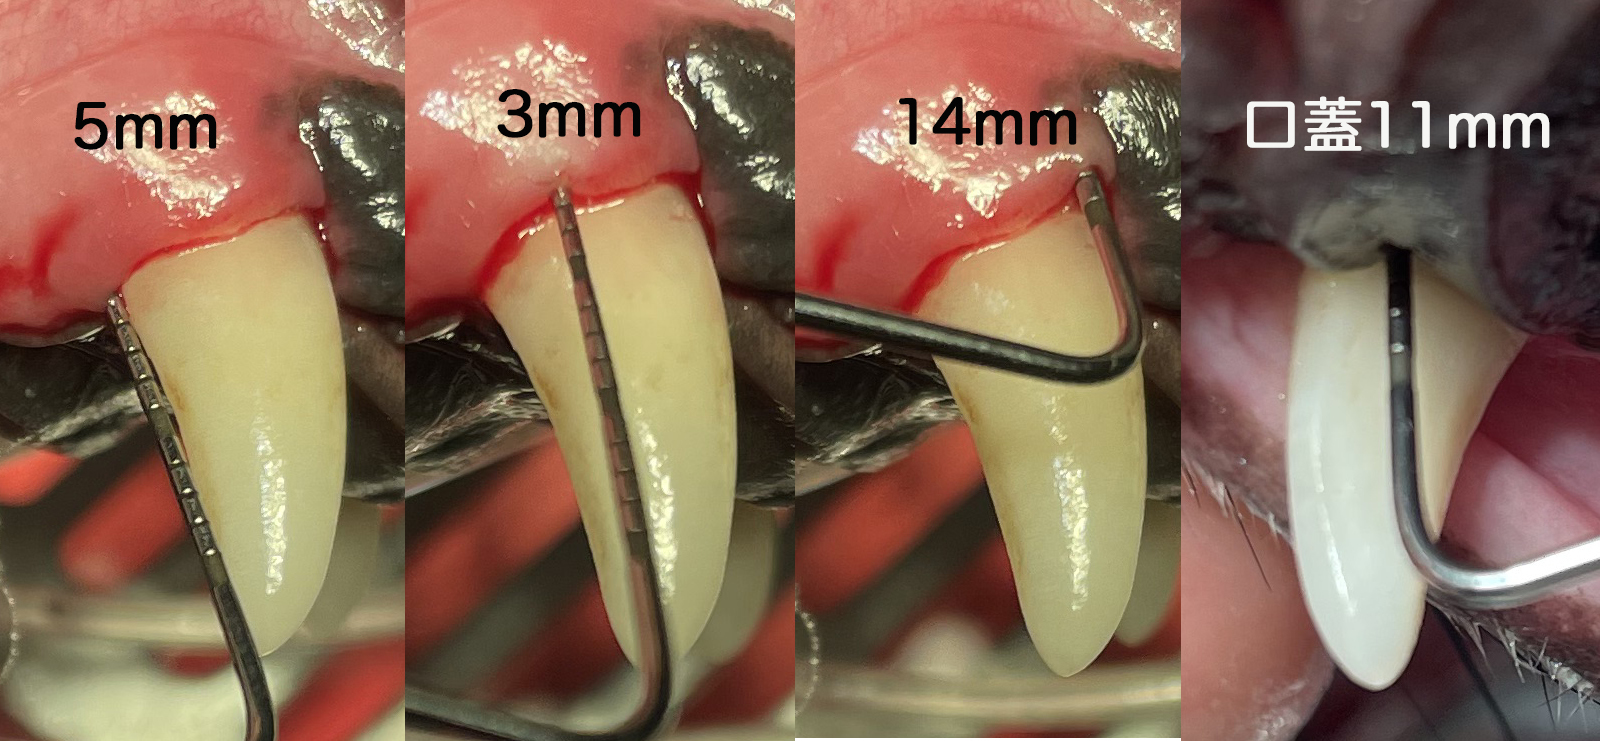

となります。ポケットが減少するのに2ヶ月を要します。当院では平均13〜15mmが3〜5mmくらいに減少し口腔鼻腔瘻になるリスクを大きく低下します。

一番左の画像は歯石を取る前ですが、この時点で歯周ポケットはあまり存在しないだろうという予想を立てます。実際、麻酔下においてポケットを計測しても近心遠心ともに3mmのポケットであり、さほど重症度は高くないと判断されます。しかし下記をご覧いただくと

同様に頬側は正常で口蓋側のポケットが深い例です。

今回は「その1」と異なり、頬側、口蓋ともに歯周ポケットが深い症例について見ていきます。頬側面は5/3/14mmであり口蓋側は11mm。このような場合には口蓋側のみの切開だけでなく頬側面も切開します。